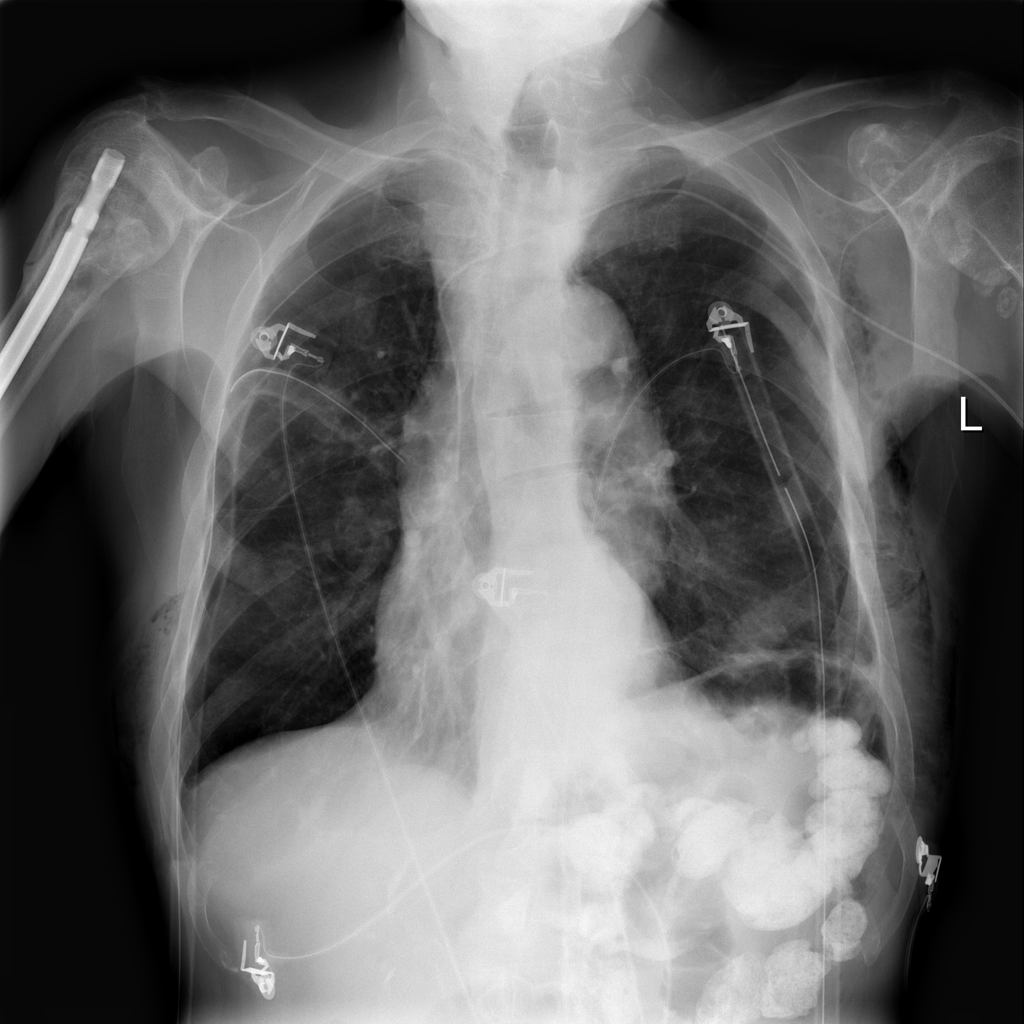

PAT-55FC · IMG-031Emphysema

PAT-55FC · IMG-031

AP